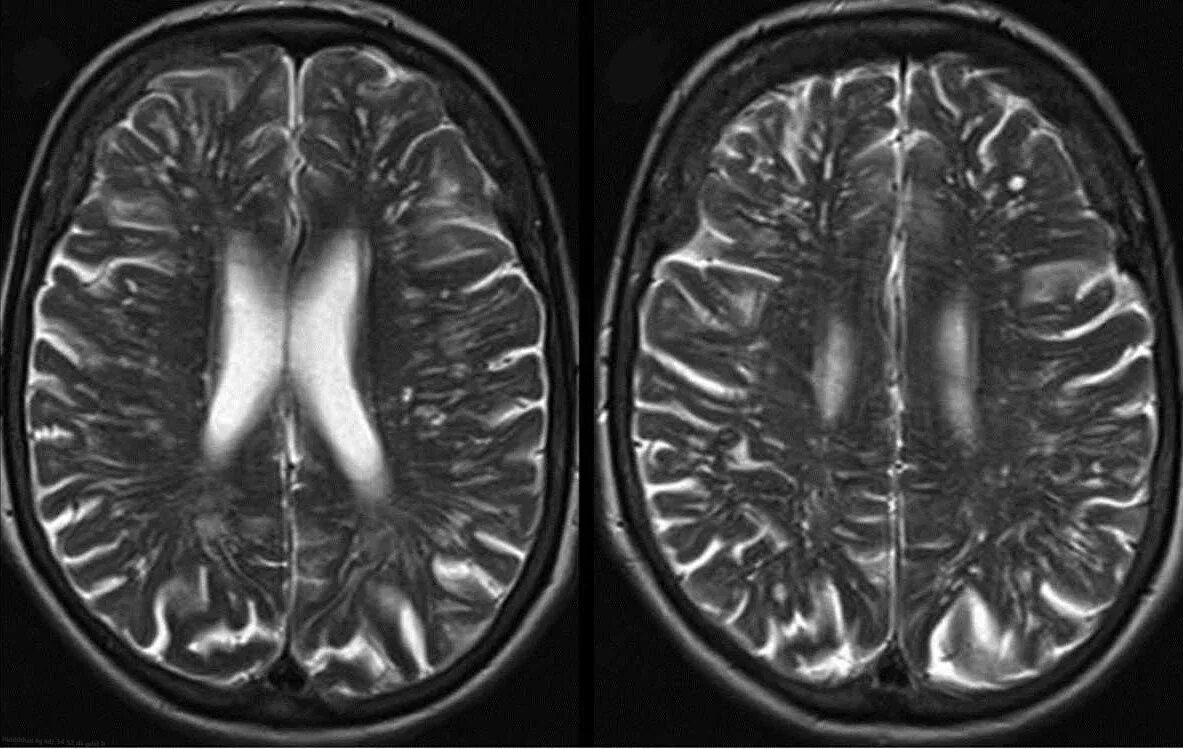

Что значит расширенные периваскулярные пространства